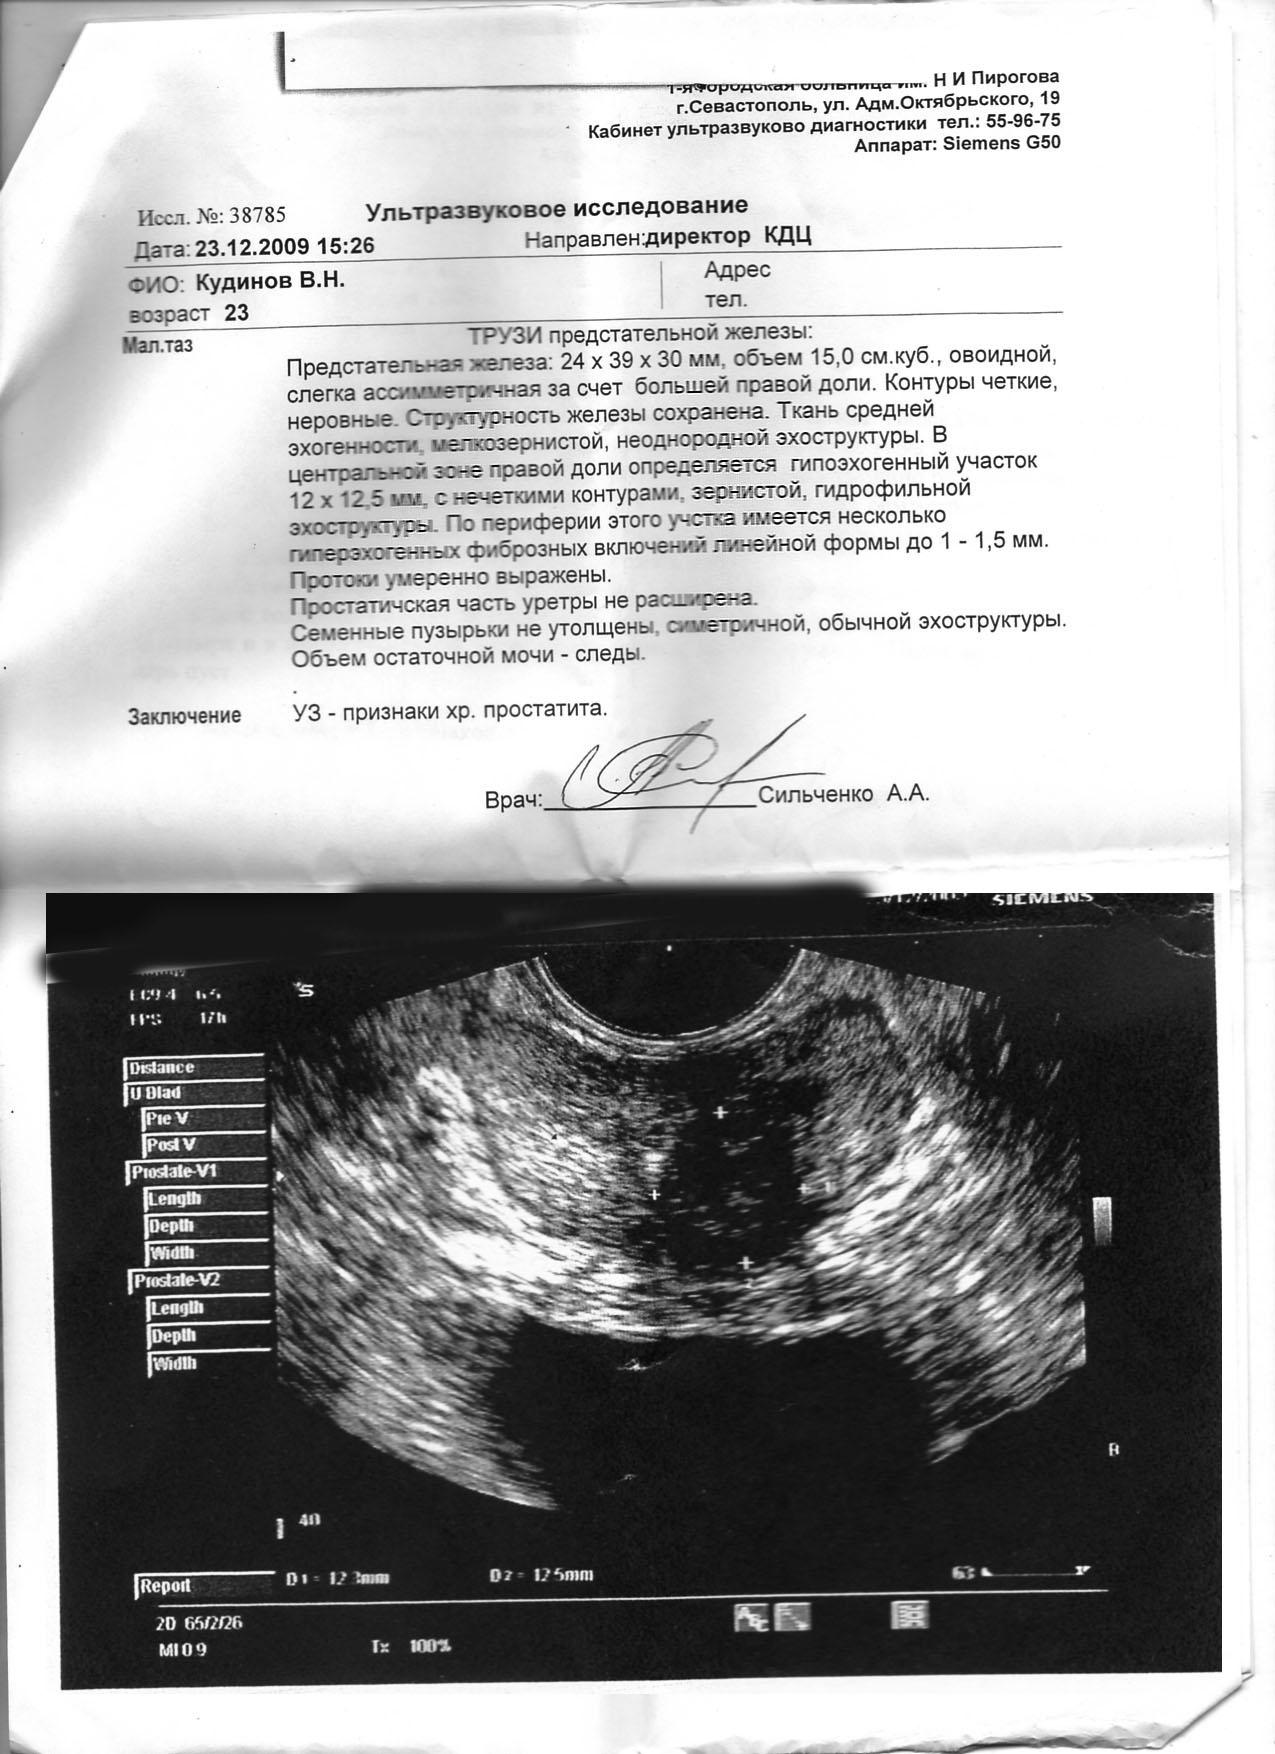

Здравствуйте доктор, спасибо огромное за ответ! Я прикреплял 2 файла Снимок и анализы, Вы не ответили по ним ничего. Если есть возможность ответитьть, ответьте пожалуйста! Если нет, то такое еще вопросик: У меня пройдет воспаление? эти самые лейкоциты уменьшатся второй анализ лучше того, что до лечения? Спасибо заранее!